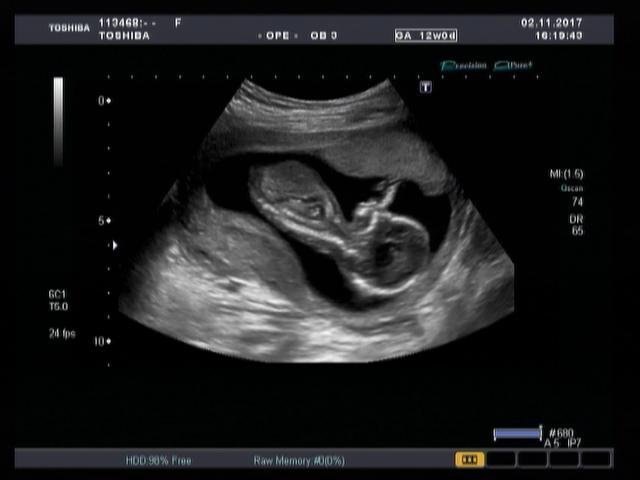

Функция автоматического измерения толщины воротникового пространства (Auto NT measurement) представляет собой инструмент для оценки размера воротниковой зоны плода, обеспечивающий превосходную воспроизводимость результатов. Эта функция позволяет проводить автоматические измерения и получать достоверные и воспроизводимые результаты при недостаточно четкой визуализации.